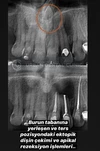

Endodonti